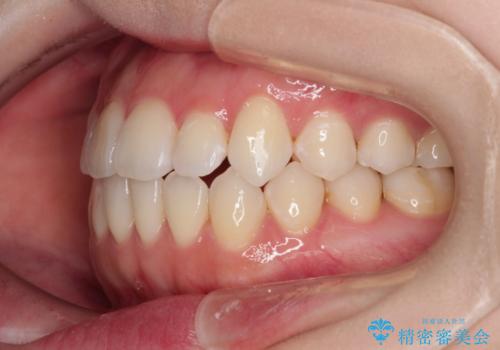

舌突出癖による開咬 舌のトレーニングを行いながら前歯の隙間を改善

- 上下前歯の隙間を気にして来院された患者様です。

前歯が、舌の突出癖により上下前歯が非接触となっている状態でした。

ワイヤー矯正での開咬改善には時間がかかります。

舌の突出癖改善のトレーニングをしっかりと行っていただき、上下前歯が接触する咬み合わせを達成することができました。